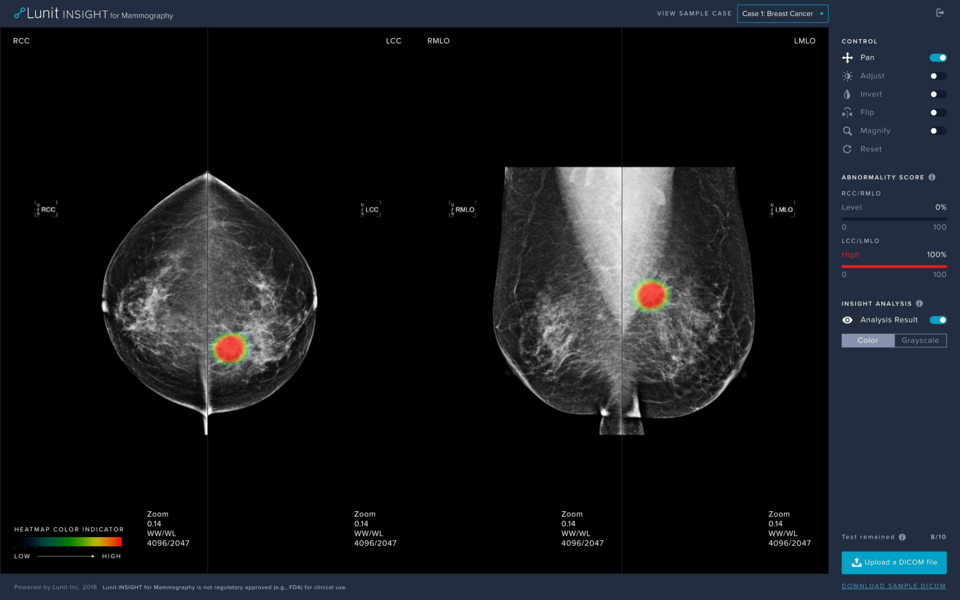

루닛은 스웨덴 스톡홀름 소재 카피오 세인트괴란 병원(이하 세인트괴란병원)에서 유방촬영술 AI 영상분석 솔루션 ‘루닛 인사이트 MMG’를 스웨덴 국가 유방암 검진 프로그램에 활용하고 있다고 지난 10일 밝혔다.

루닛은 올해 초 스웨덴 최대 사립병원인 세인트괴란병원과 루닛 인사이트 MMG를 3년간 공급하는 라이선스 계약을 체결한 바 있다. 현재 세인트괴란병원은 유방암 진단을 위한 이중 판독 과정에서 의사 한 명 대신 루닛 인사이트 MMG를 적용해 유방촬영술 판독을 하고 있다.

유럽 일부 국가와 호주 등에선 유방암 검진 시 영상의학과 전문의 2명이 이중 판독을 하도록 강제하고 있으며, AI가 실제 의료 환경에서 의사 두 명 중 한 명을 대체해 최종 진단까지 담당하는 경우는 이번이 처음이다. 세인트괴란병원의 연간 유방촬영술 판독 건수는 18만 건에 달하는 것으로 알려졌다.

이번 연구는 유방암 검진 시 영상의학과 전문의 2명이 이중 판독해야 하는 일부 유럽 국가의 암 검진 환경을 반영해 ▲전문의 2명 ▲루닛 AI+전문의 1명 ▲루닛 AI 단독으로 진단하는 경우로 나눠 각각의 결과를 비교 분석했다.

연구 결과, 수검자 1,000명당 암 발견율은 AI+전문의 1명이 4.3, 전문의 2명이 4.1, AI 단독이 4.1로 나타났다.

이에 대해 루닛 측은 “자사 AI와 전문의 1명을 결합한 경우가 전문의 2명이 판독한 경우보다 암을 더 많이 발견한 것으로 나타났다”며 “루닛 AI 단독으로 판독하더라도 전문의 2명이 판독한 것과 비교해 암 발견율이 열등하지 않은 것으로 확인됐다”고 평가했다.

암 재검사를 위해 환자를 다시 소환하는 리콜률(Recall Rate, RR)의 경우, 수검자 100명당 리콜률은 AI+전문의 1명이 2.8, 전문의 2명이 2.93, AI 단독이 1.55로 나타났다.

루닛 측은 “루닛 AI와 전문의 1명을 결합한 경우가 전문의 2명이 판독한 경우보다 리콜률이 낮았다”며 “루닛 AI 단독으로 판독한 경우, 전문의 2명이 판독하는 경우보다 리콜률이 현저히 낮았다”고 강조했다.